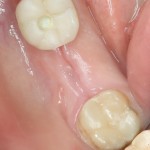

В боковом сегменте зубного ряда лучше просто оставить лунку заживать так, как есть:

и все нормально заживет. Через 1.5-2 месяца вы получите нормальные условия для имплантации: